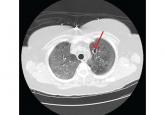

ArticleDisseminated invasive aspergillosis in an immunocompetent patientAuthor:Jessica McLaughlin, DOPublish date: June 3, 2019The patient, who has COPD, will require lifelong antifungal treatment.Read More